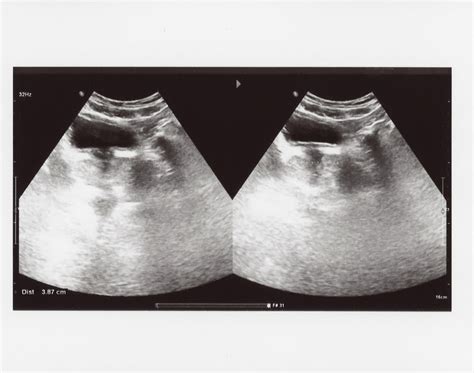

Prima ecografie de confirmare a sarcinii se efectuează la patru săptămâni după embriotransfer. În acest moment se poate confirma viabilitatea și localizarea intrauterină a sarcinii, prin constatarea embrionului cu activitate cardiacă. De obicei, evaluările ecografice și recomandările de tratament până la morfologia de primul trimestru se efectuează prin medicul specialist în infertilitate, iar ulterior pacienta este preluată de către medicul care îi va urmări sarcina până la final.

La două săptămâni după transfer se face un test de sarcină. Dacă acesta este pozitiv, atunci se continuă cu medicația prescrisă. La cinci săptămâni după transfer, veniți la primul ecograf. În același timp, se poate determina dacă poziția embrionului în uter este cea corectă și dacă dezvoltarea acestuia este conformă cu săptămâna de sarcină. În momentul în care se constată activitate cardiacă la embrionul dumneavoastră, terapia FIV se consideră încheiată și veți fi transferată pentru supraveghere la medicul dumneavoastră specialist.